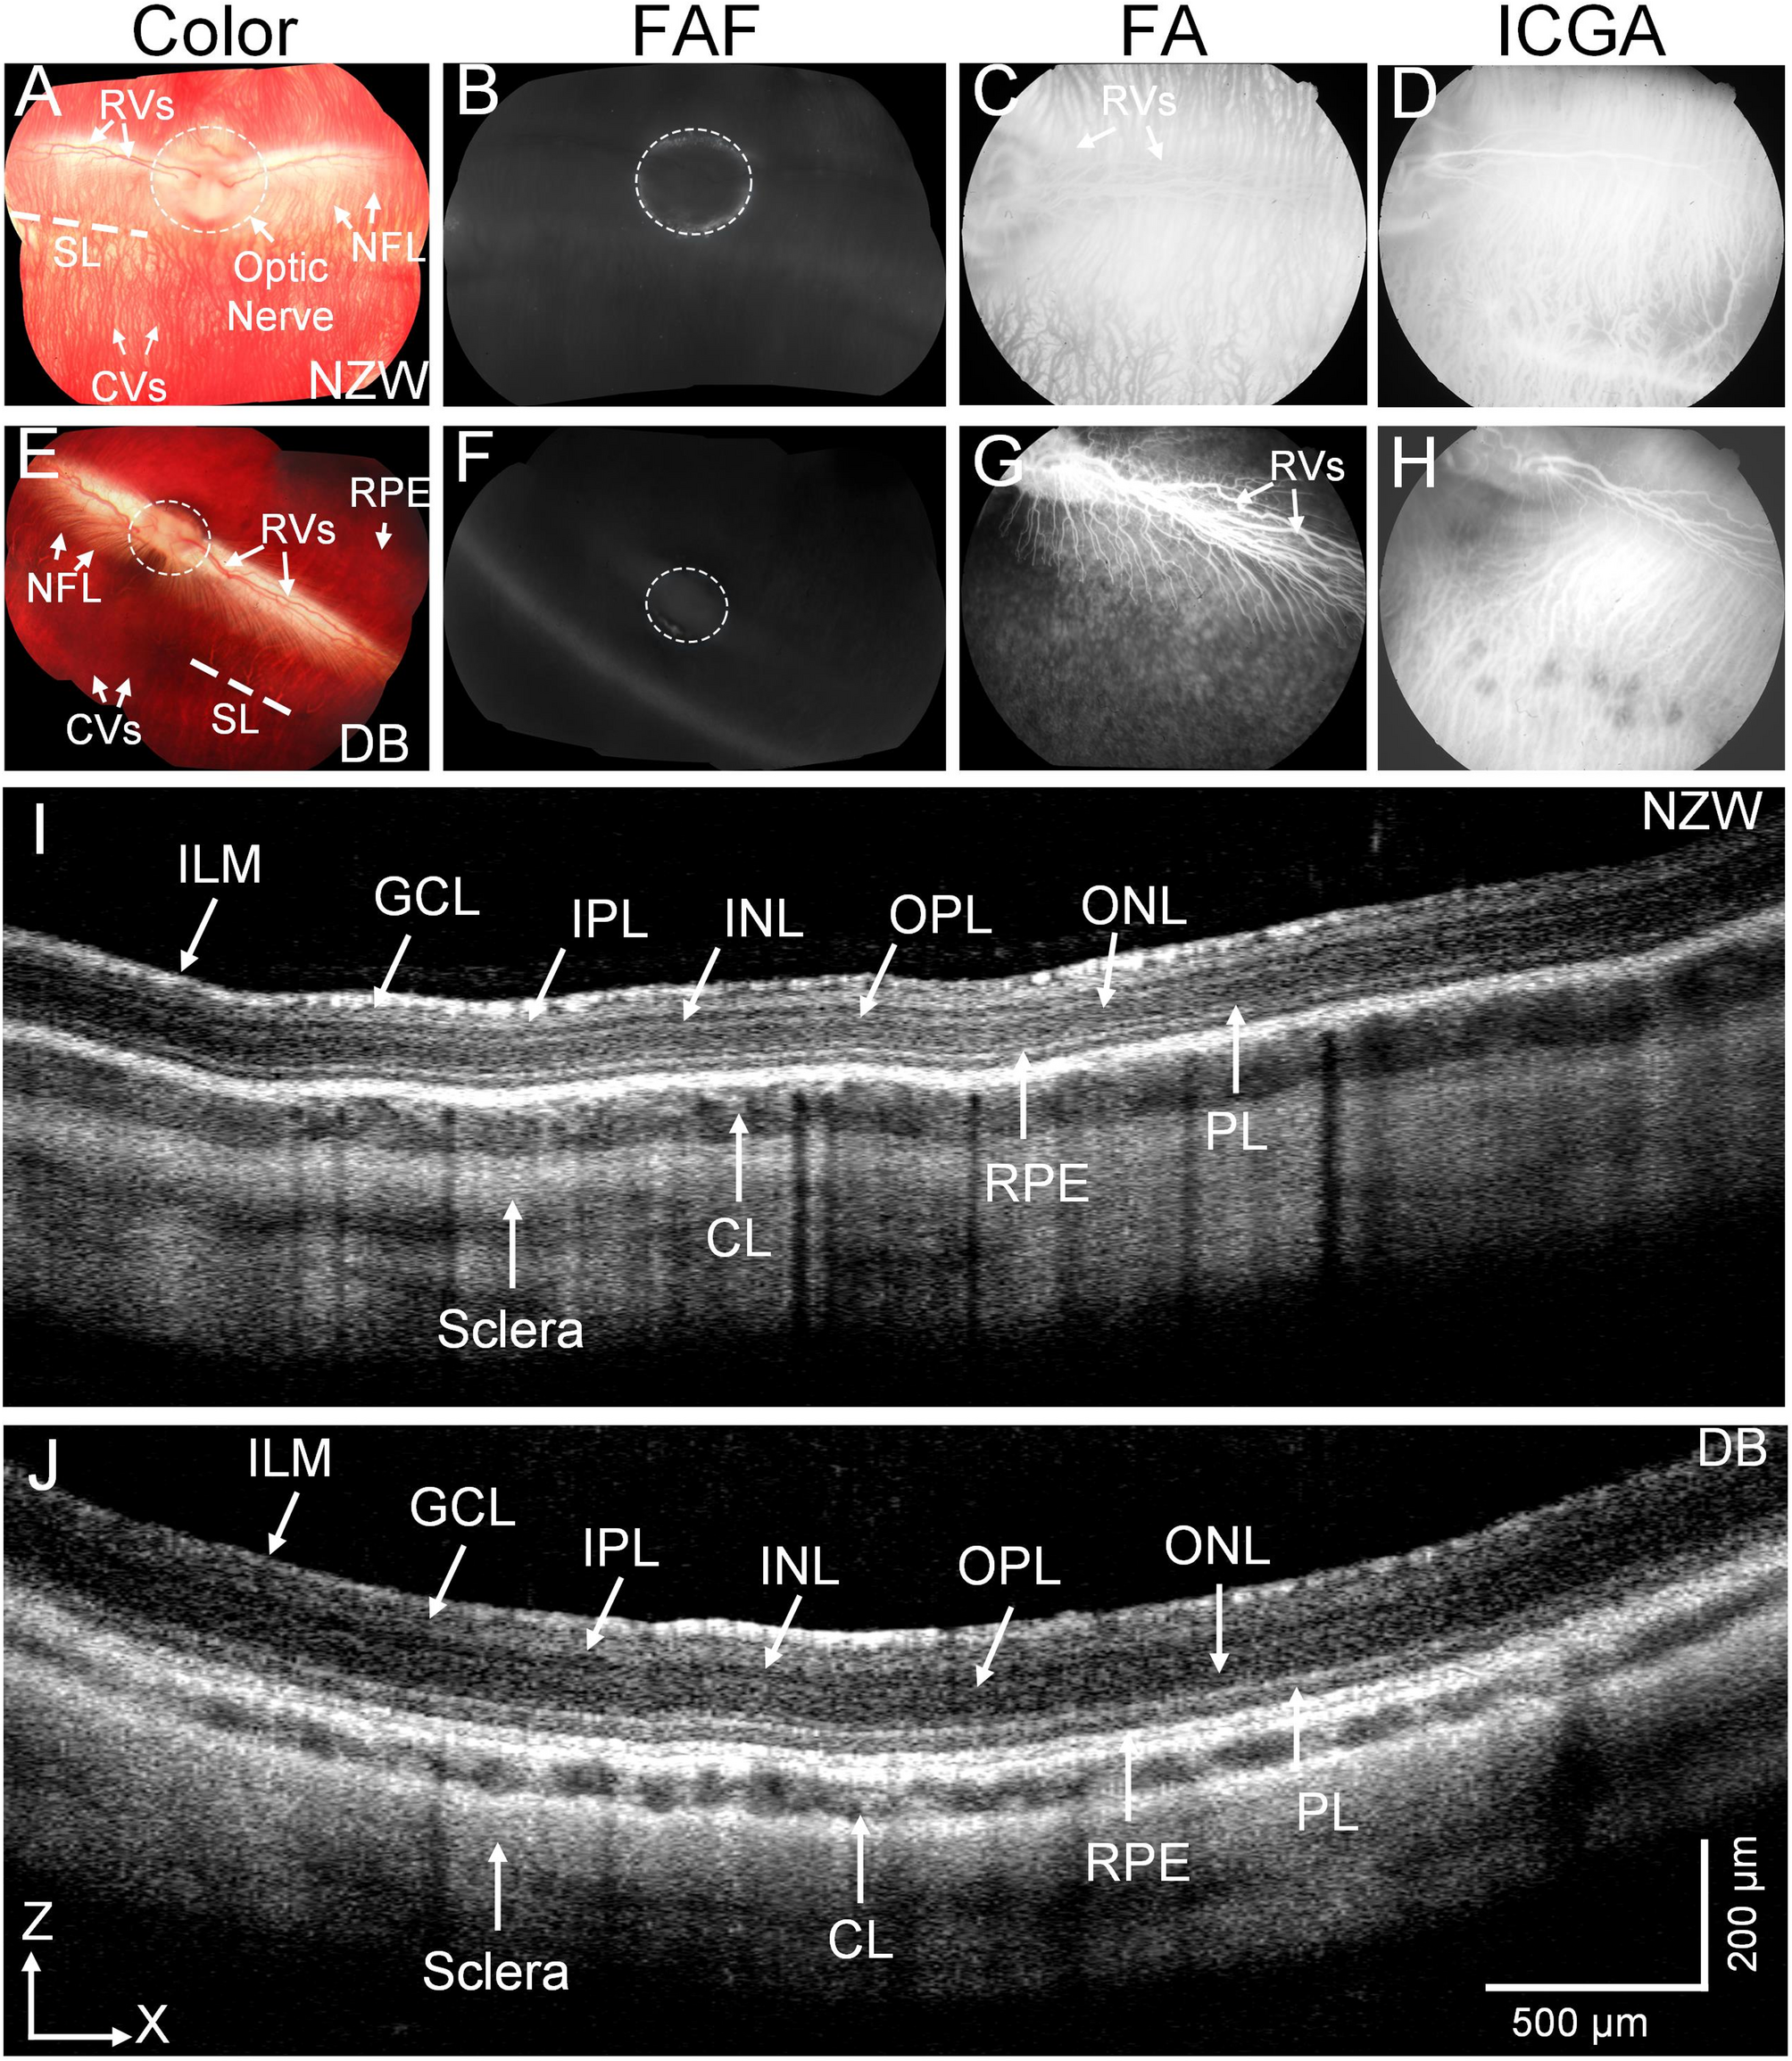

Fig. 1

Multimodal imaging of New Zealand White (NZW) and Dutch-belted (DB) Rabbit retina: (A and E) Color fundus photography image of NZW (A) and DB (E) rabbits, respectively. These images clearly show morphology of retinal vessels (RVs), nerve fiber layer (NFL), choroidal vessels (CVs), retinal pigment epithelium (RPE), and optic nerve (white dotted circles). (B and F) Fundus autofluorescence images showing healthy retina without any evidence of RPE atrophy. (C and G) Fluorescein angiography of NZW and DB, respectively. (D and H) Indocyanine green angiography images clearly show structure of the choroidal vessels. (I and J) B-scan spectral domain OCT (SD-OCT) images demonstrating the cross section retina constructed from different layers such as inner limiting membrane (ILM), ganglion cell layer (GCL), inner plexiform layer (IPL), inner nuclear layer (INL), outer plexiform layer (OPL), outer nuclear layer (ONL), photoreceptor layer (PL), choroid layer (CL), and sclera. The OCT scan region of interest is indicated by scanning lines (SL) and marks as red dotted lines overlay on the fundus photographs (a and d), corresponding to the rabbit’s visual streak. This region was chosen for its high photoreceptor density and relevance to retinal function as a structure akin to the human macula.